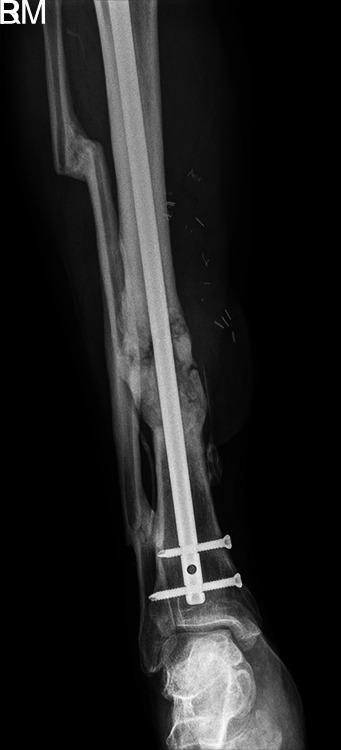

Case description: Difficulties were encountered removing a tibial nail which was deeply sunk into the proximal tibia from its entry point. Therefore, the fracture site was exposed, and the nail was cut. The proximal portion was removed in a retrograde fashion. Removing the distal end of the nail posed a dilemma after standard techniques failed, but it was successfully extracted by threading a Schanz pin into the exposed cannulated portion of the nail and then backslapping a T-handle.

Conclusion: This is a novel technique for the removal of an incarcerated segment of a cannulated tibial nail from the distal tibia when other techniques were unsuccessful.

Clinical significance: The novel method presented in this case report allows for extraction of a sunken tibial intramedullary nail when extractor seating is difficult to obtain and the incarcerated distal segment of a cannulated tibial nail cannot be removed by standard techniques.